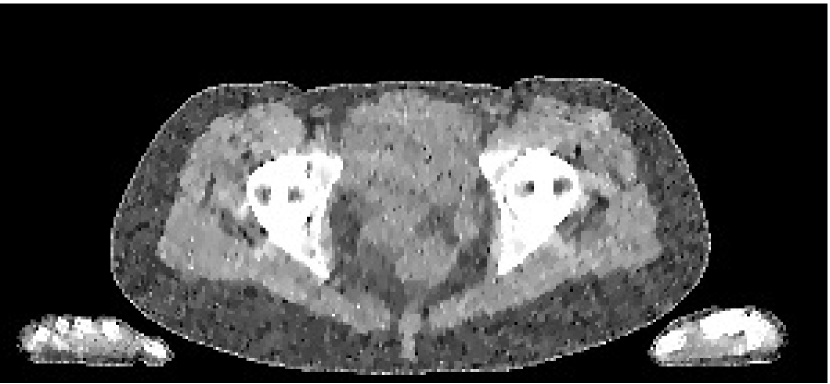

The data we used for our numerical reconstruction test were derived from the Adult Reference Computational Phantom (ICRP Publication 110,, 2009), which is a segmented image of defined density and chemical composition to represent real tissues. To investigate the ability to image metal implants, we inserted a pair of prosthetic hip joints (marked in green) with a solid titanium pin and shell. The slices through the chest and pelvis—which are the images we selected for testing—are shown in Figure 8. The resolution is 299×137299137299\times 137.

Refer to caption

(a) Chest test image

(b) Pelvis test image

Figure 8: Experimental data used: (a) is the oracle chest electron density; and (b) is the oracle pelvis electron density; both have a with display window of [0.8,1.2]